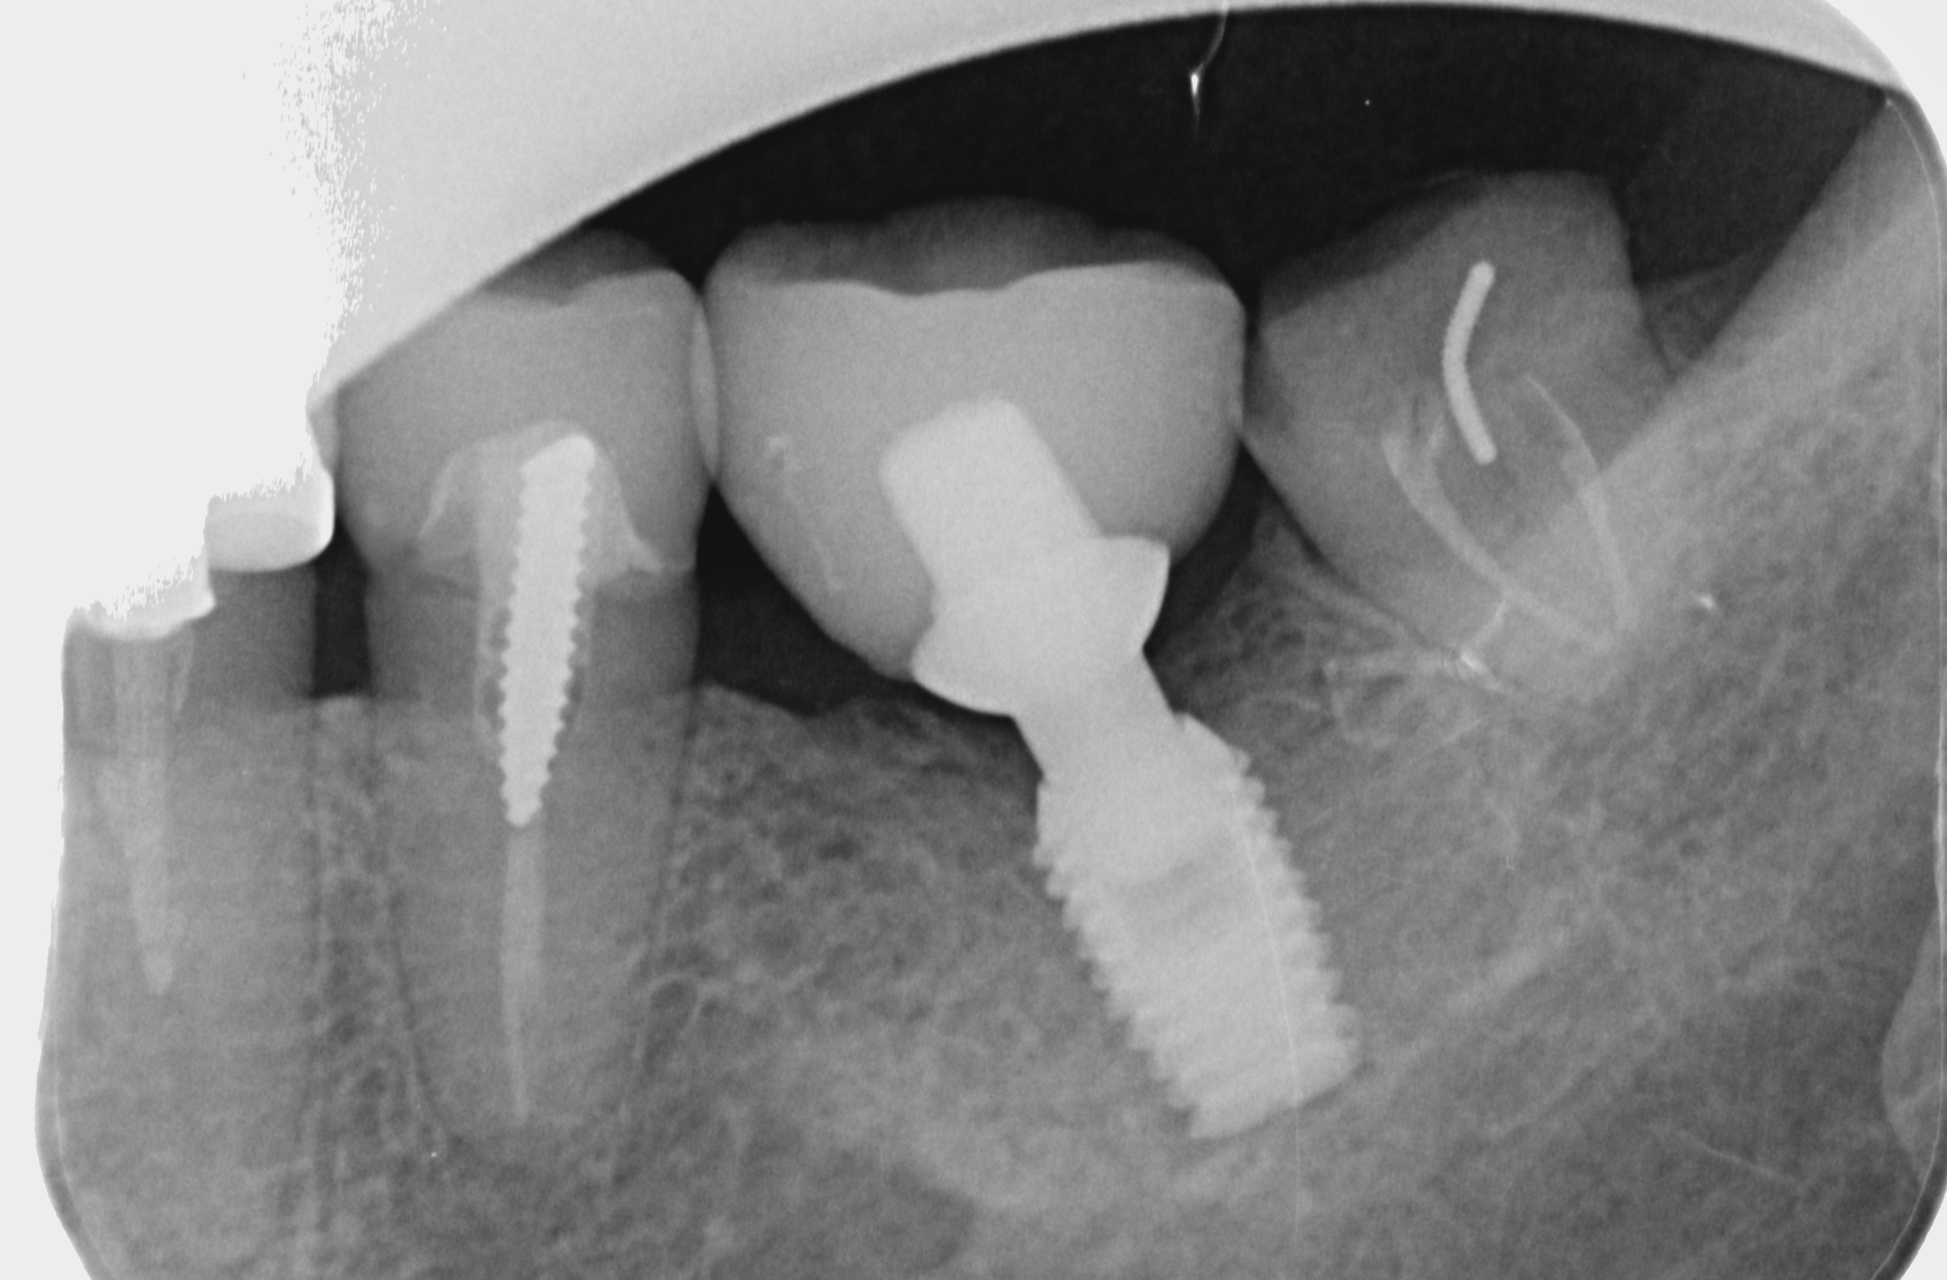

Wenn Zähne längere Zeit fehlen, kommt es zu einer Knochenresorption des Kieferkammes in Breite oder Höhe. Werden dann Implantate gewünscht, kann es sein, dass ein Knochenaufbau nötig wird.

Hierbei gibt es verschiedene Techniken wie Grafting, Ridge Splitting oder Sinuslift. Ist jedoch noch ein geringer Teil von Knochen vorhanden, besteht die Möglichkeit von Kurzimplantaten. Um die Möglichkeiten dieser Therapien abzuschätzen ist eine genaueste Diagnostik wichtig.

Wenn Zähne längere Zeit fehlen, kann es dadurch bedingt zu einer Knochenresorption kommen. In weiterer Folge kann es sein, dass zu wenig Knochen für ein Implantat vorhanden ist. Oft werden dann aufbauende Operationen wie Knochenerweiterung oder Knochenaufbau nötig.

Manchmal kann es jedoch auch sein, dass noch genug Knochen vorhanden ist und man sich diese zusätzlichen Operationsschritte erspart. Lassen Sie sich bei einem Beratungsgespräch über die Möglichkeit von Kurzimplantaten beraten.